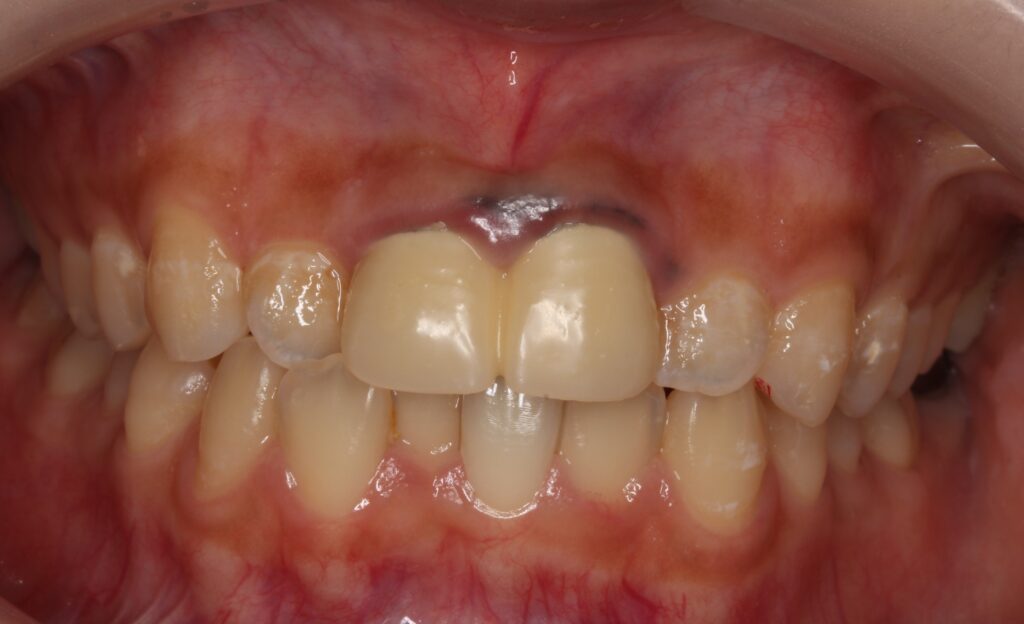

お口の中を見ると

前歯2本にかぶせ物が入っており、その歯ぐきが黒く変色しています。

これは金属が溶け出し歯ぐきの中に入り込んでしまった状態で、「メタルタトゥー」と呼ばれます。

前歯のかぶせ物は「レジン前装冠」といい、内部に金属を使用しています。

表面はレジンというプラスチック樹脂を張り付けています。